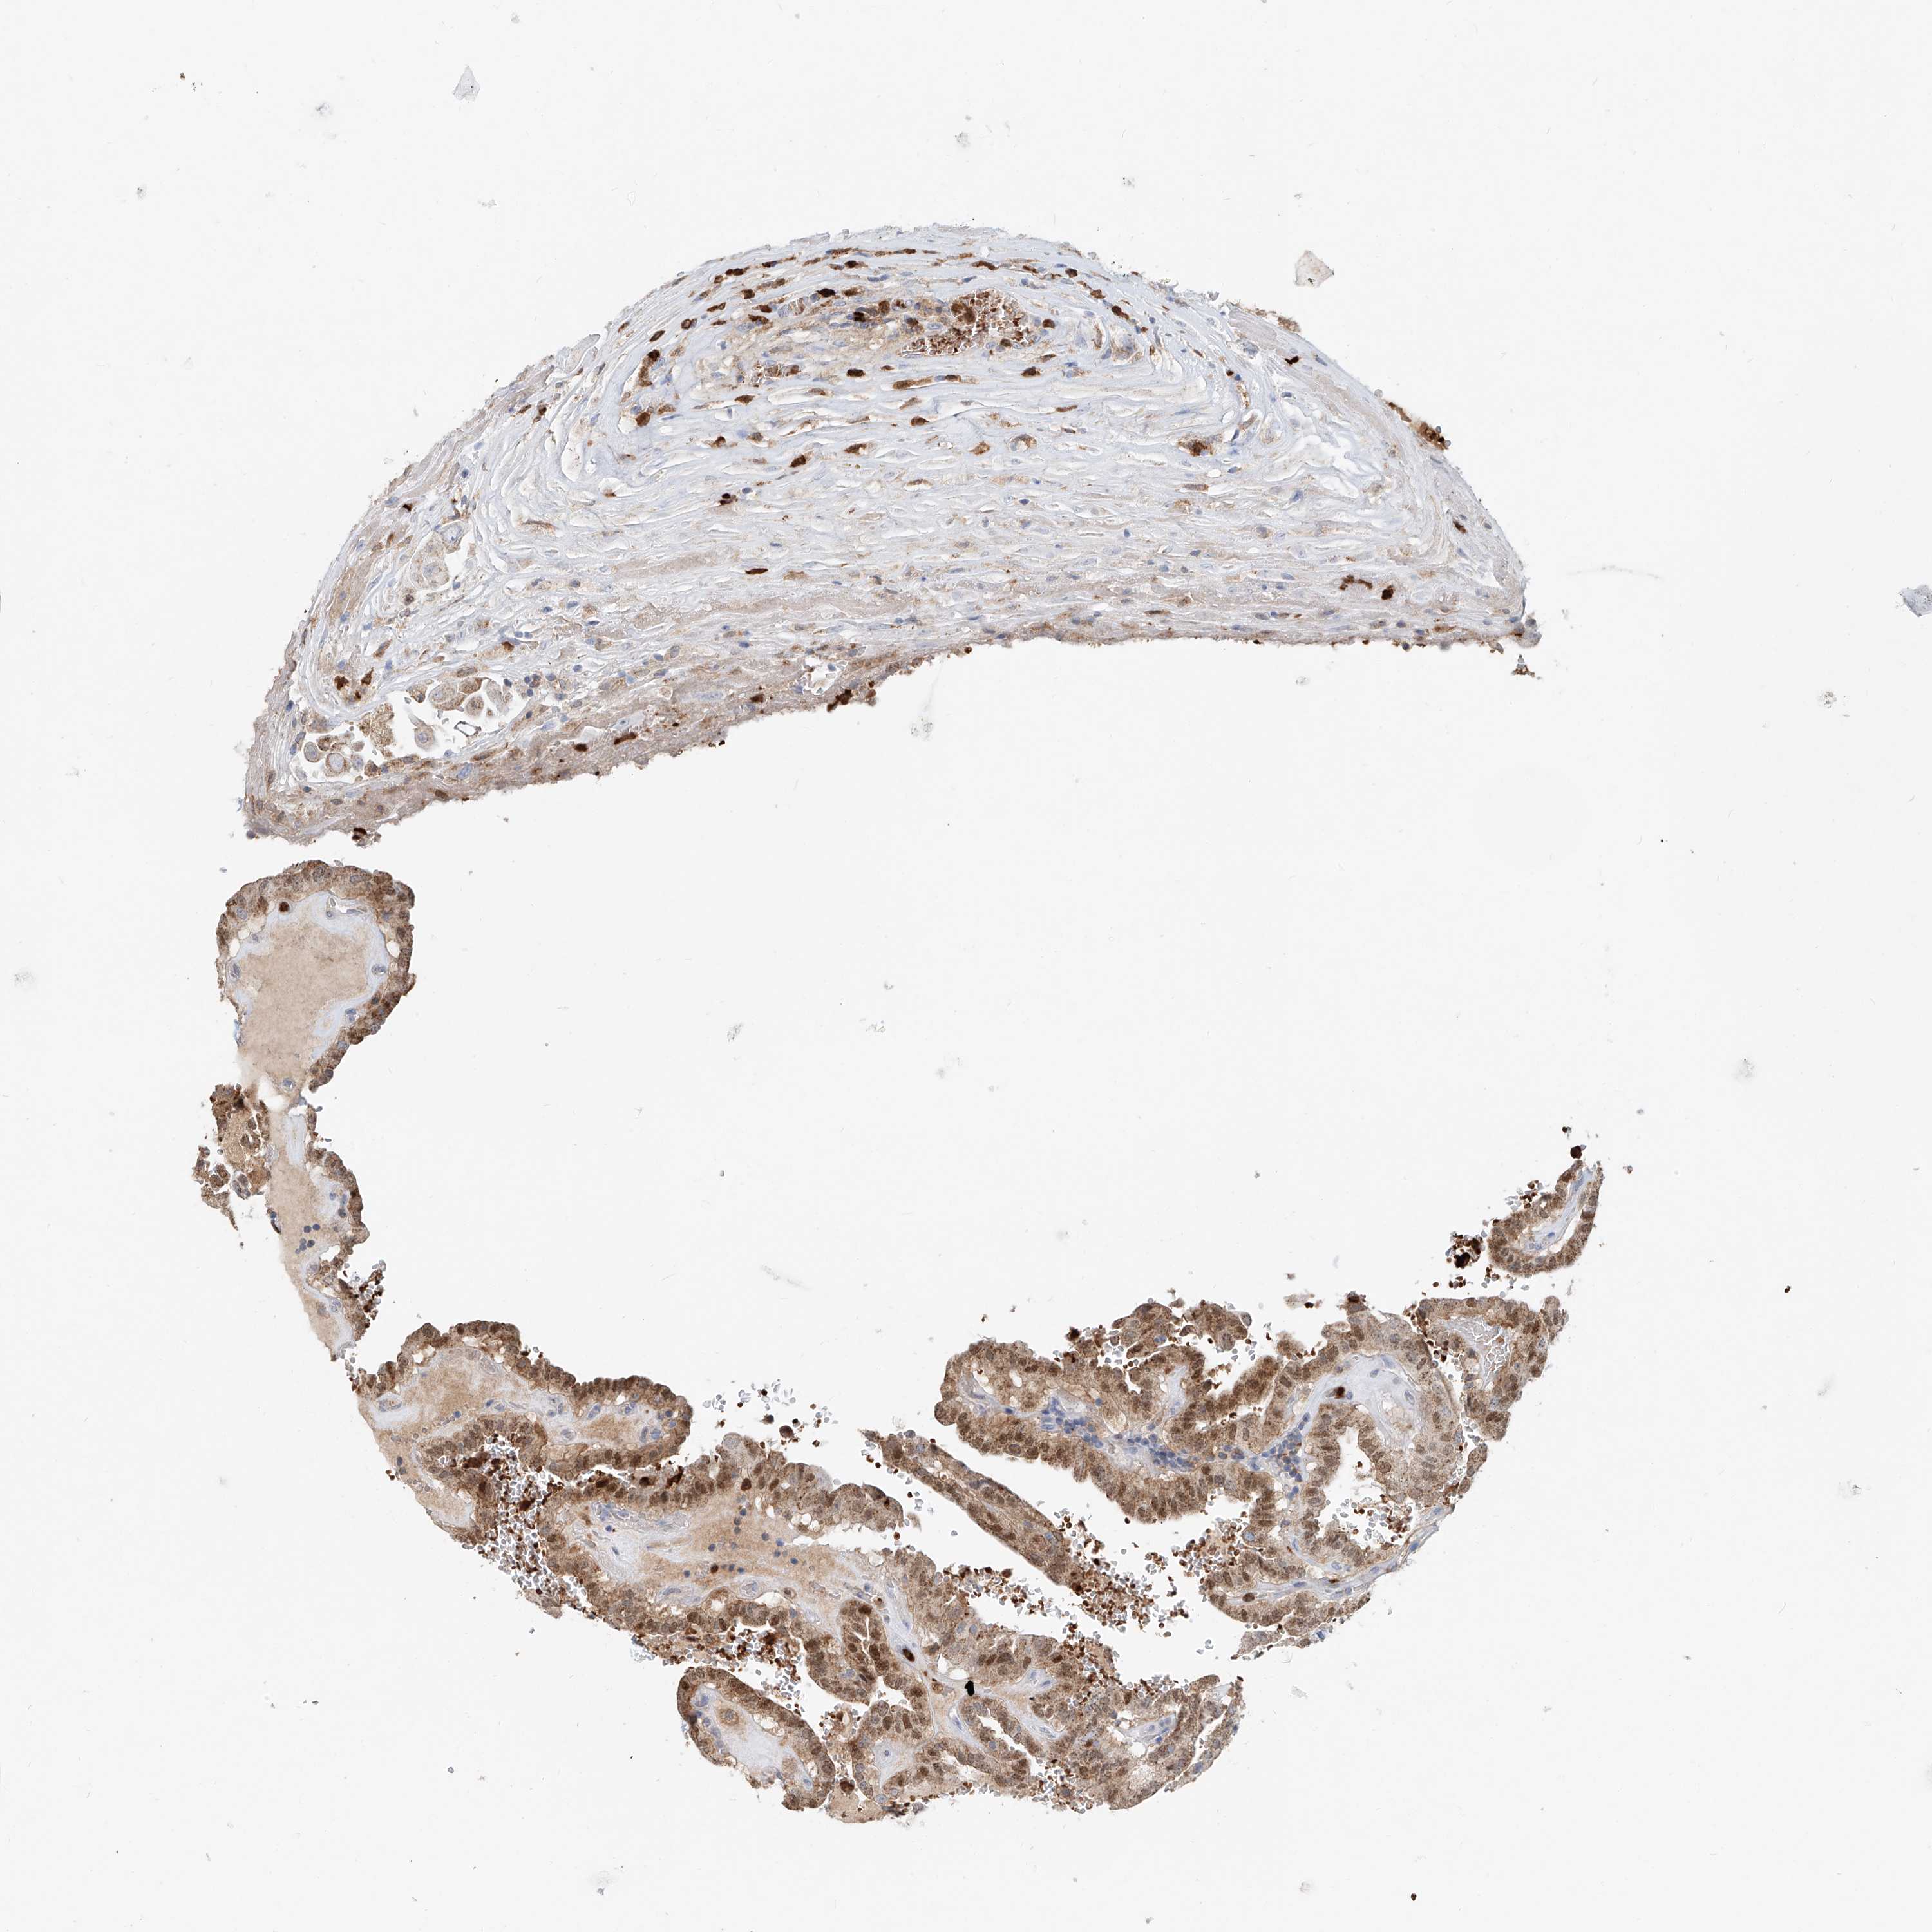

THYROID CANCER - Protein expressioni

A mouse-over function shows sample information and annotation data. Click on an image to view it in a full screen mode. Samples can be filtered based on level of antibody staining by selecting one or several of the following categories: high, medium, low and not detected. The assay and annotation is described here.

Note that samples used for immunohistochemistry by the Human Protein Atlas do not correspond to samples in the TCGA dataset.

Antibody stainingi

Antibody staining in the annotated cell types in the current human tissue is reported as not detected, low, medium, or high, based on conventional immunohistochemistry profiling in selected tissues. This score is based on the combination of the staining intensity and fraction of stained cells.

Each image is clickable and will lead to virtual microscopy that enables deeper exploration of all samples and also displays staining intensity scores, fraction scores and subcellular localization as well as patient and tissue information for each sample.

Antibody HPA029412

Antibody CAB034366

Staining

High

Medium

Low

Not detected

Intensity

Strong

Moderate

Weak

Negative

Quantity

>75%

75%-25%

<25%

None

Location

Nuclear

Cytoplasmic/membranous

Cytoplasmic/membranous,nuclear

Papillary adenocarcinoma, NOS

Follicular adenoma carcinoma, NOS